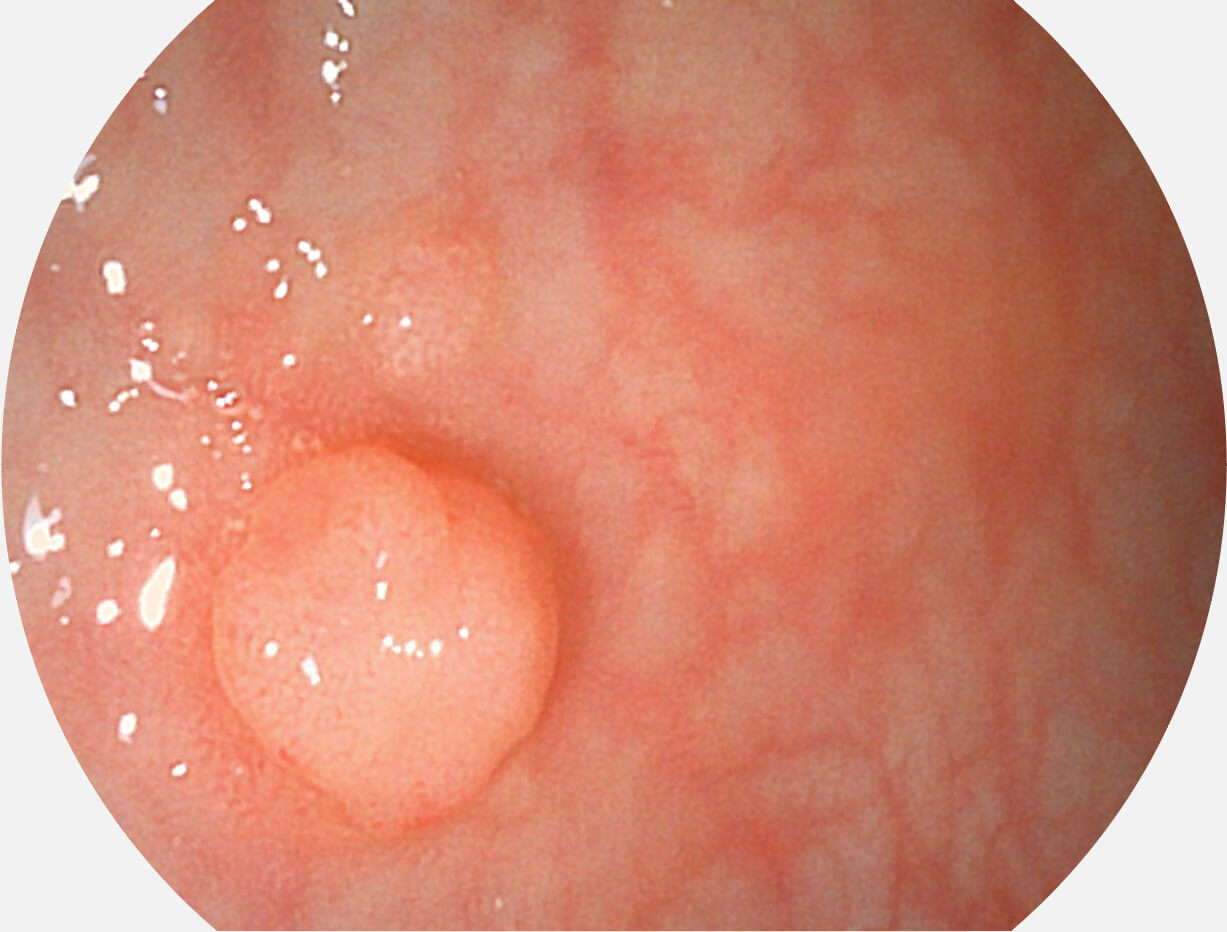

白光图像

SFI图像

图像具有高亮度、高黏膜血管颜色对比度的特点,且不改变粘液、食物残渣、粪便的基本颜色,可在中远景下进行观察,助力消化道早期疾病的诊断。